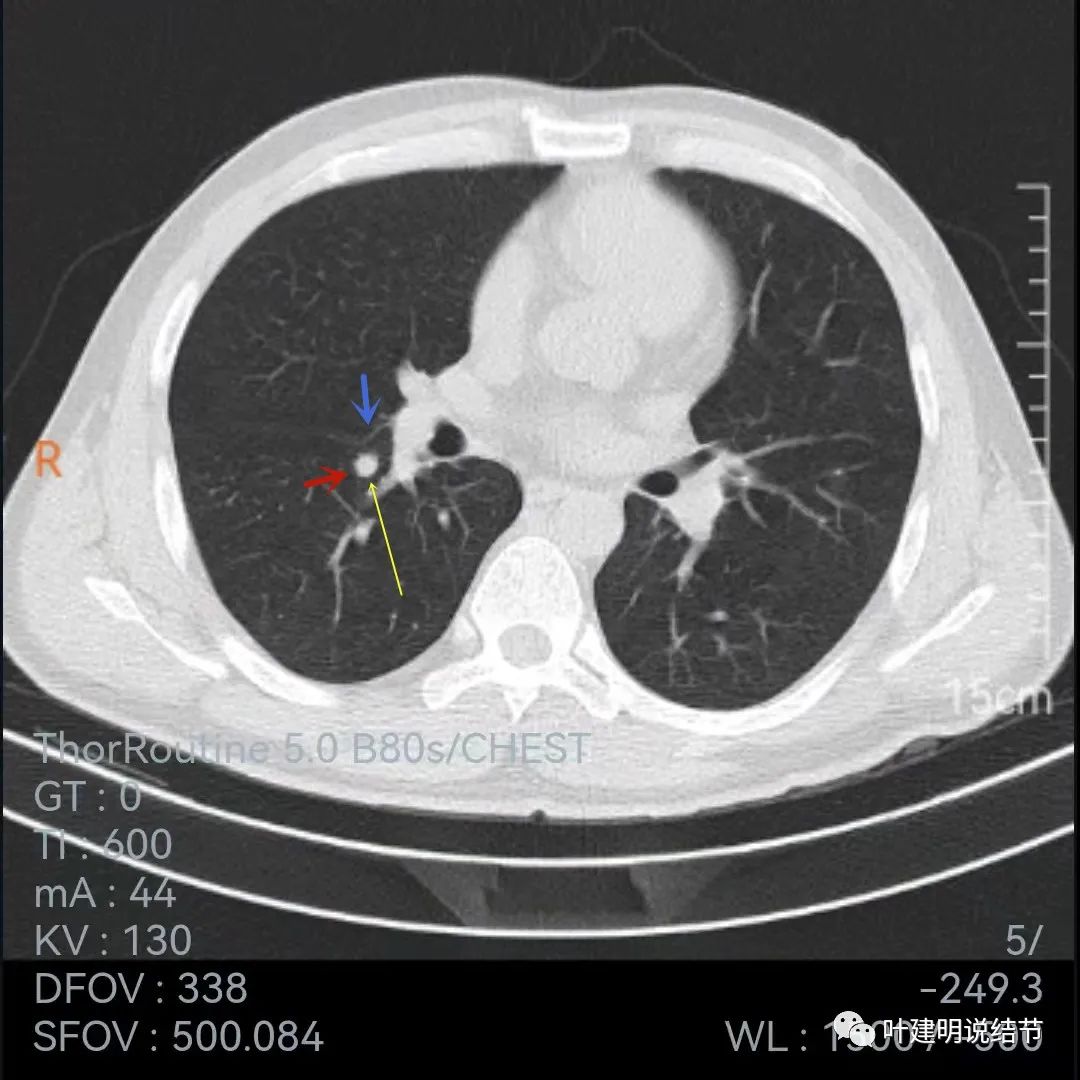

再看下面2020年7月的平扫片子:

非薄层的看,病灶还是小结节,实性,边缘似乎比前一年略有毛糙,胸膜轻微牵拉,黄色箭头所指似乎病灶中央的密度比周围部分略低,会不会是肉芽肿性炎伴有少许坏死?